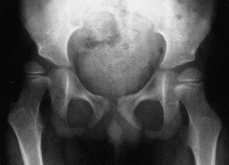

Figura 3. Ejemplo pre y postoperatorio tras la osteotomía, en una cadera derecha subluxada y con displasia acetabular, que por su edad se trató con una osteotomía de fémur.